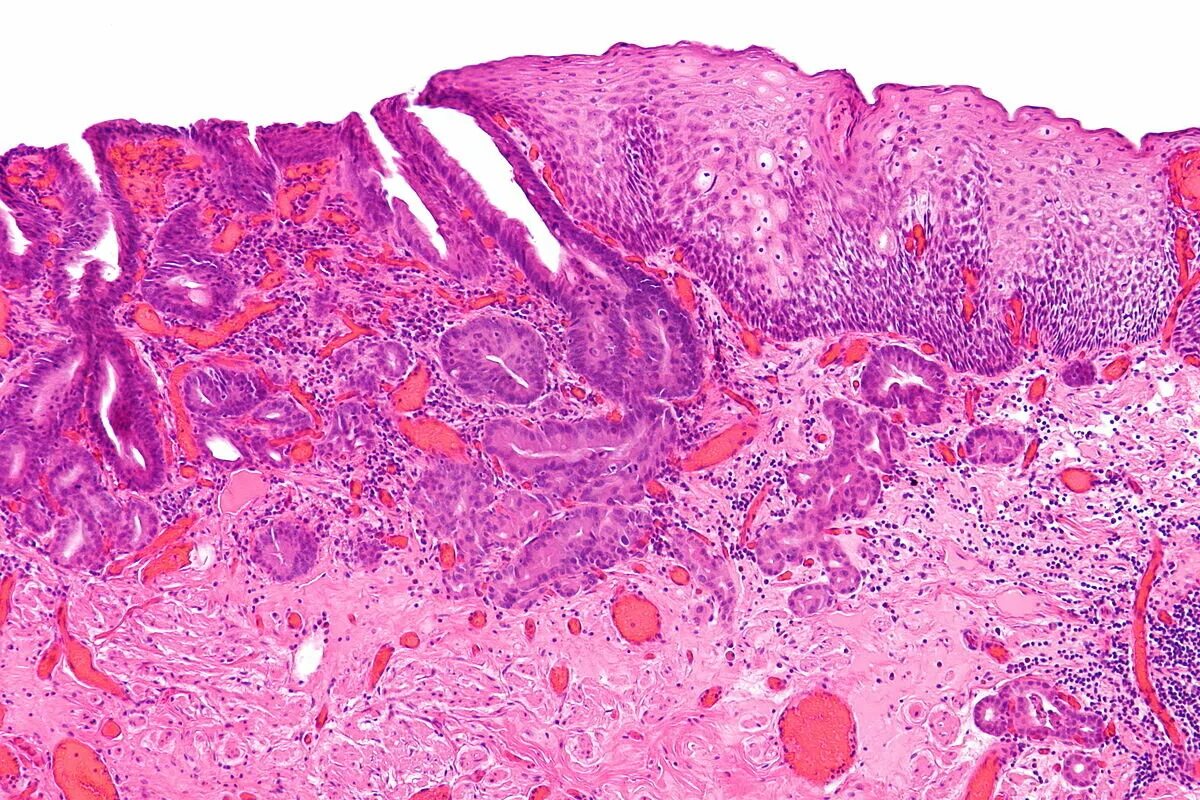

Про гистология